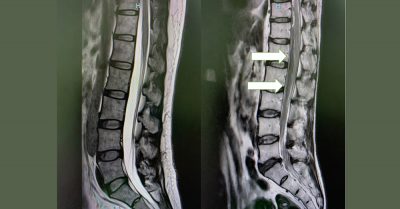

家人担心他中风了,急忙招了救护车,把他送回去国家心脏中心。做了脑部扫描后,中风的可能性被排除,但波叔的情况还是没有好转。再进一步扫描脊柱,才发现是脊椎硬膜外出血,血块压迫第九胸椎(T9)至 骶椎(S1)的脊椎神经,导致椎管狭窄,进而造成马尾症候群和脊髓圆椎受损,令波叔下肢麻痛、双脚无力和大小便失禁。

波叔万分无奈,但也乖乖听话,入住加护病房,暂停服用双抗血小板药,小心控制血压,祈祷出血没有加剧。48至72小时后做磁力共振扫描,谢天谢地,出血受控了,我让他转到普通病房,继续观察和进行复健。